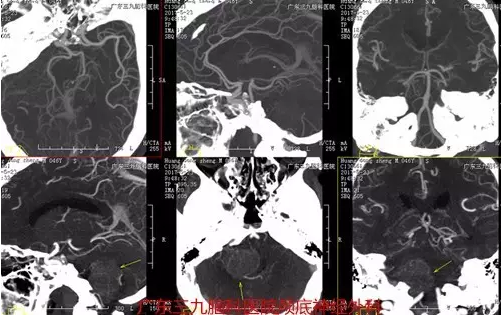

图3:术前CTA提示肿瘤血供极丰富